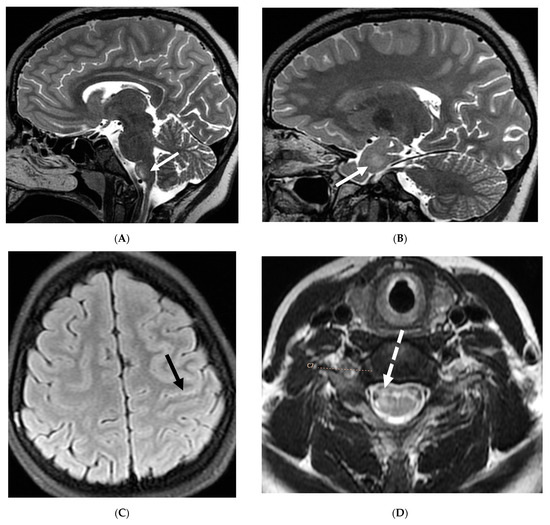

Intracranial hypotension in children is frequently secondary to iatrogenic causes including lumbar punctures, craniospinal surgeries and ventricular shunt drain pressure changes [64]. Spontaneous causes are commonly connective tissue disorders such as Marfans and Ehler Danlos syndromes. Dural tears and meningeal diverticula have been demonstrated in these cases [65]. Beyond headaches, IH can manifest with nausea, vomiting, light sensitivity (photophobia), and stiff neck [66].

MRI features of IH can be explained by the Monroe-Kellie doctrine, which states that the intracerebral volume including blood, CSF and brain parenchyma remain the same. Thus, a decrease in CSF volume promotes dilatation and rounding of the venous sinuses, subdural fluid collections along with dural (pachymeningeal) enhancement which occurs due to vascular engorgement and transudation of fluid into it [67]. Hyperemia of the pituitary gland occurs which may mimic hyperplasia or pituitary tumor. Brainstem slumping or downward displacement of the brainstem, defined as red nuclei below the tentorium and low lying third ventricle below the sella, are highly specific indicators of IH, observed in half the cases. A pontomesencephalic angle of less than 50 degrees and mamillo pontine distance of less than 5.5 mm are sensitive and specific parameters to suggest IH [66].

With regard to spine imaging, in addition to the intracranial features of dural enhancement, venous engorgement and subdural collection, unique findings include meningeal diverticula, dural ectasia and C1–C2 sign (Figure 8 and Figure 9). Additionally, a CT myelogram may identify the precise location of the CSF leak which can be sealed off with a blood patch [65,68].

Figure 8.

Sagittal T1 (A), post axial T1 (B,C), axial CT myelogram (D) and technetium 99 m DTPA SPECT-CT (E): 16-year-old with Gorham’s disease. There is cerebellar tonsillar herniation and decrease in prepontine cisterns (white arrows). Significant increase in the size of the venous sinuses (dashed arrow). Diffuse pachymeningeal enhancement is seen (black arrows). Cystic-appearing foci at the skull base are in keeping with lymphangiomatosis with contrast pooling into the lytic lesion (curved arrow). Abnormal radiotracer extravasation in the left clival region correlating with lytic lesion (open arrow). Features are in keeping with intracranial hypotension secondary to CSF leak.

Figure 9.

Sagittal T2 FS (A), sagittal (B) and axial (C) T1 post contrast: 3-year-old with neck pain post LP. There is diffuse epidural thickening, with increased T2 signal and enhancement, throughout the cervical, thoracic and lumbar spine (white arrows). Several prominent flow voids are seen within the anterior epidural thickening in the upper cervical region (dashed arrow). There is also increased high T2 signal between the occiput and posterior arch of C1, and between the posterior arch of C1 and spinous process of C2 (curved arrows) in keeping with “C1–C2 sign”. Findings are related to intracranial hypotension post lumbar puncture.